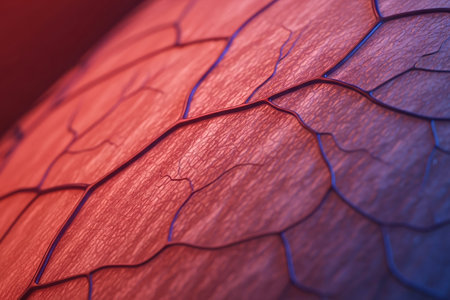

Macro view of human blood vessel network with red and blue tones showing capillaries and vein structure, ideal for illustrating medical anatomy and biology research.

Detailed visuals showcase the complex network of blood vessels in human anatomy.

A detailed view of red blood vessels intertwines across a soft gradient background. The intricate network showcases the complexity of human circulation highlighting the various sizes and shapes of the vessels

Human red blood vessels in vein close up. 3d illustration.

Vessel flow texture in red and blue lighting showing microscopic circulation system pattern symbolizing human biology, anatomy, and healthcare science visualization.

Human blood veins, red vessels

Detailed visualization of intertwined red capillaries resembling a biological network, set against a dark blue backdrop